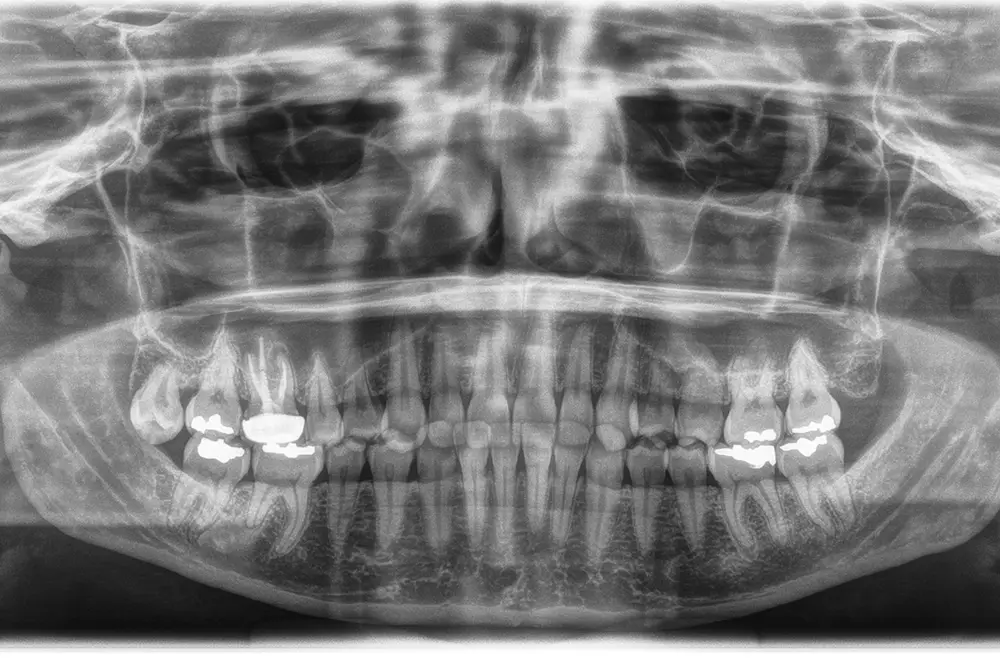

En este caso, la paciente acude con la exodoncia realizada hace dos años de la pieza 16 y una gran atrofia vertical, existiendo únicamente 1 mm en algunas zonas de la cresta, como el área más vestibular, y hasta 3 en la zona más palatina (fig. 9). Procedemos a la realización del fresado tal como se ha descrito en el caso anterior y colocamos el mismo tipo de injerto (autólogo y PRGF- Endoret) y un implante de 4,5 mm de longitud (fig. 10 y 11). Tras la cicatrización a los 4 meses, observamos el aspecto de la zona de la colocación del implante, donde tenemos ahora una altura de 7 mm (fig. 12).

Llegados a este punto, se retira el implante de 4,5 mm al igual que en el caso anterior, de forma totalmente atraumática, y se coloca un implante de 6,5 mm de longitud (fig. 13). Se realiza la carga del implante a los 4 meses y tras 3 años de seguimiento comprobamos la estabilidad total del tratamiento realizado (fig. 14).

Fig. 9. Cone-beam de planificación donde observamos la escasa altura residual de la cresta a nivel de la pieza 16.